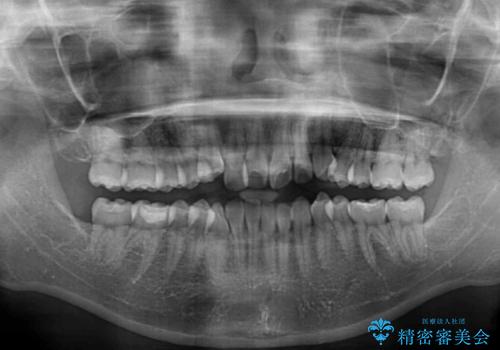

- 前歯のデコボコを治したいとのことで来院された患者様です。

インビザラインによるマウスピース矯正も適用となる歯列でしたが、できる限り楽して、短期間で治したいとのことで、ワイヤー装置にて矯正治療を行うこととしました。